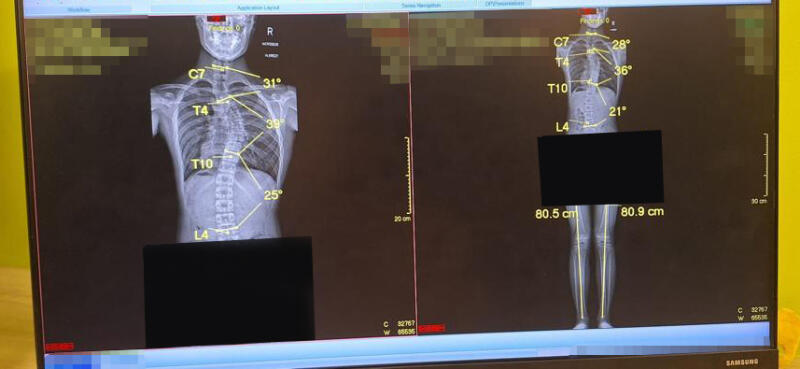

她说,X光结果显示儿子的背椎向右倾了36度,腰椎则向左倾21度,脊椎骨呈S形。

刘晓娥透露,儿子接受十多次中医推拿,大约3个月后,于去年12月回到医院照第二次X光,结果发现情况没好转,脊椎骨的弯曲程度反而更严重了。

“胸、腰椎弯曲的度数分别增加了3度和4度。我当初找上的中医师曾承诺,推拿后‘度数减少一半’。